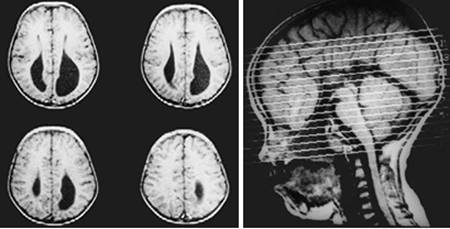

Figure 7

Clinical and image aspects of patient 7

Int J Med Sci Image